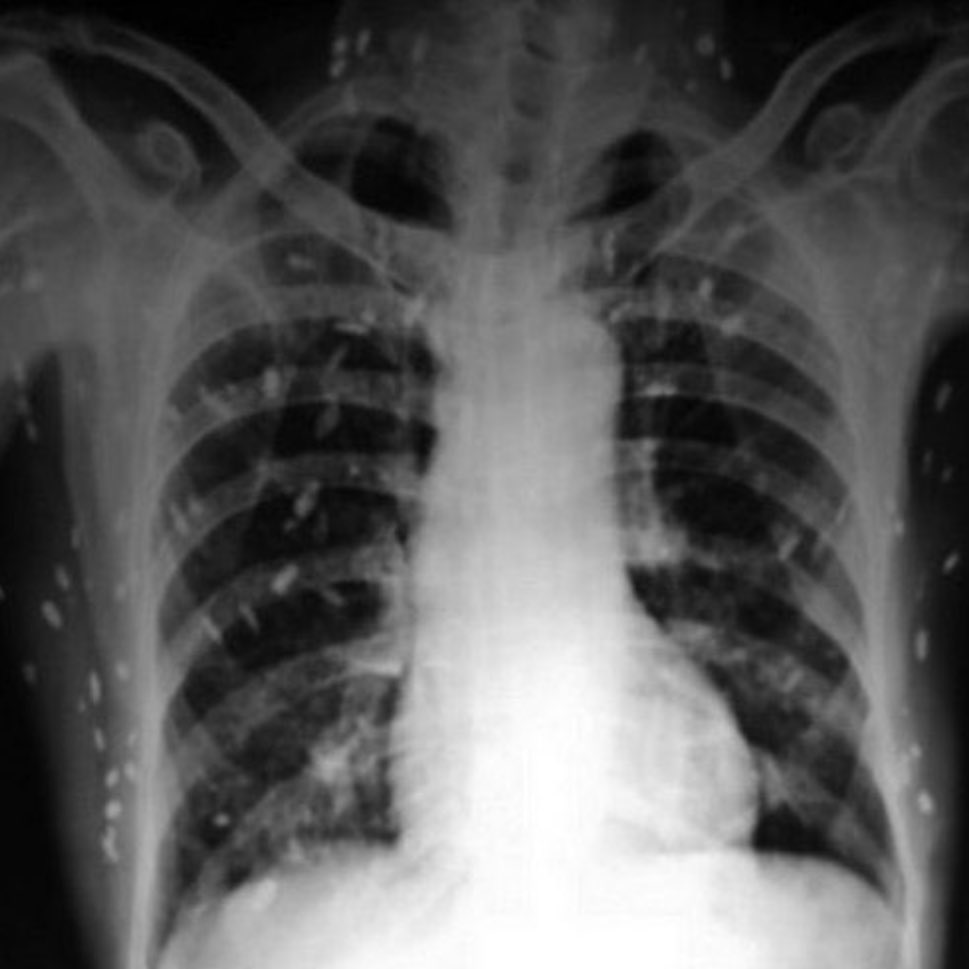

Yurtdışında bir Hasta, parmaklarında ve bileklerinde ağrı ve sızı şikayetiyle hastaneye başvurdu. — Fiziksel muayene, kan testleri ve göğüs röntgeninden sonra doktor hemen tüm vücut röntgeni çekilmesini istedi. Radyografi sonucu:

Yurtdışında bir Hasta, parmaklarında ve bileklerinde ağrı ve sızı şikayetiyle hastaneye başvurdu.

— Fiziksel muayene, kan testleri ve göğüs röntgeninden sonra doktor hemen tüm vücut röntgeni çekilmesini istedi.

Radyografi sonucu: